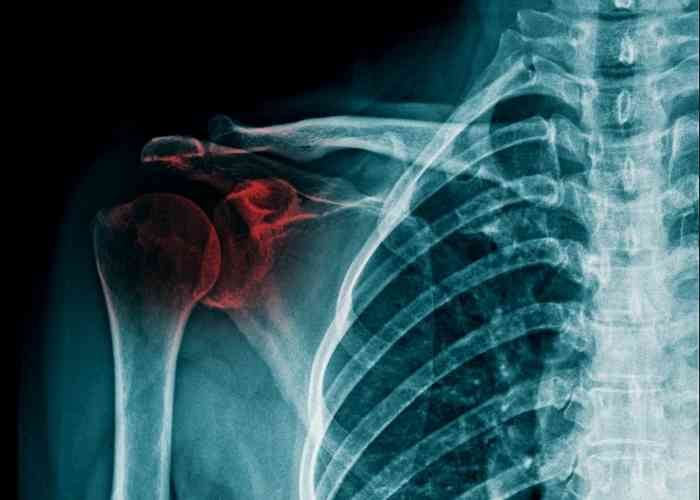

사고로 어깨뼈가 골절되었을 때, 관련된 입원 기간, 수술 후 물리치료 및 도수치료 비용, 그리고 실비보험 적용 여부에 대해 알아보겠습니다. 어깨 골절은 예상치 못한 상황에서 찾아올 수 있으며, 대비하기 어려운 사건입니다. 저 또한 몇 년 전에 어깨뼈 골절로 인한 치료를 받은 적이 있습니다. 이 글에서는 어깨뼈 골절 치료와 관련된 주요 내용을 다룰 것입니다.

어깨뼈 골절의 입원 기간은 다양하며 상황에 따라 다를 수 있습니다. 일반적으로 어깨 골절의 경우 상완골 골절로 분류되며, 핀고정 수술이 필요한 경우 보통 1주에서 2주 정도의 입원 기간이 필요합니다. 그러나 교통사고나 다른 상황으로 어깨뼈 골절이 더 복잡한 경우에는 입원 기간이 더 길어질 수 있습니다. 따라서 개별 환자의 상태와 치료 방법에 따라 입원 기간이 결정됩니다.

어깨뼈 골절 수술 후, 입원 중에는 주로 진통제가 투여되어 통증을 관리합니다. 이로써 입원 중에는 통증이 그리 심하지 않게 느껴질 수 있습니다. 상완골 골절의 경우 핀고정 수술이 주로 시행되며, 수술 후에는 상완골의 고정이 유지됩니다.